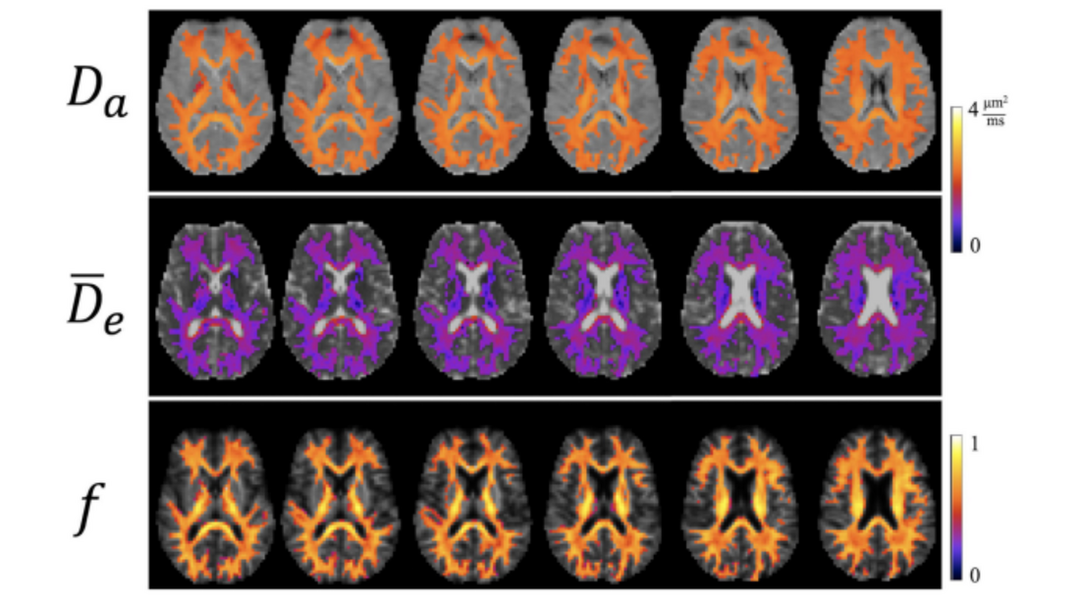

We are an interdisciplinary team at the Medical University of South Carolina united by our study of Alzheimer's disease and related dementias via diffusion MRI.

Advanced dMRI